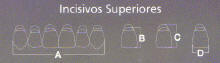

La mayoría de los fabricantes de dientes acrílicos en Sudamérica

como O' Dent (Argentina), Duratone (Colombia) y Ruthinium

(Brasil) determinan el ancho

de los seis dientes antero-superiores de esta forma.